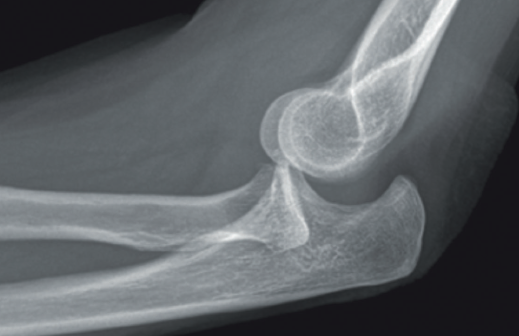

- Radiografía simple: puede orientarnos hacia una inestabilidad si se objetivan signos indirectos, tales como calcificaciones en la inserción ligamentosa, que sugieran antecedente de avulsión ligamentosa (Figura 7).

Signos de haber tenido fracturas en la cabeza del radio o la coronoides, aunque ya estén consolidadas, nos ponen en el contexto de un posible antecedente de luxación acompañando a las fracturas. También la presencia de fractura con fragmento cortical posterolateral del húmero, que ha sido considerado como el “Hill-Sachs del codo”(12)(Figura 8).

Y, por supuesto, signos directos, si objetivamos la articulación claramente subluxada (Figura 9).